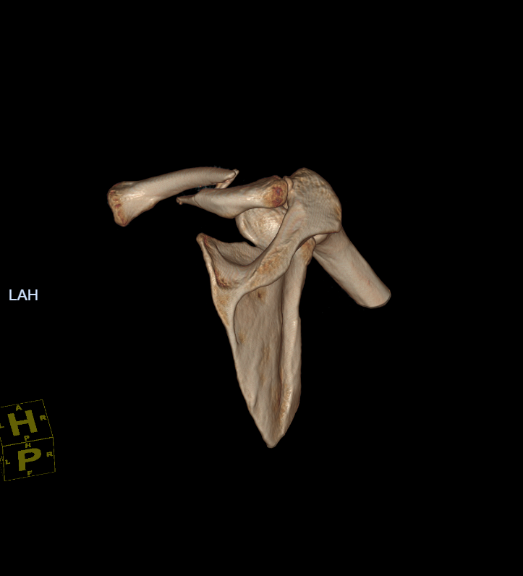

病例六:患者,男,71岁,因“摔伤致右肩部疼痛伴活动受限1小时余”入院。诊断:右锁骨骨折;行右锁骨骨折切开复位内固定术;手术顺利,术后恢复良好,顺利出院。

右锁骨骨折 术前X线片 右锁骨骨折 术前三维CT

右锁骨骨折 术后X线片